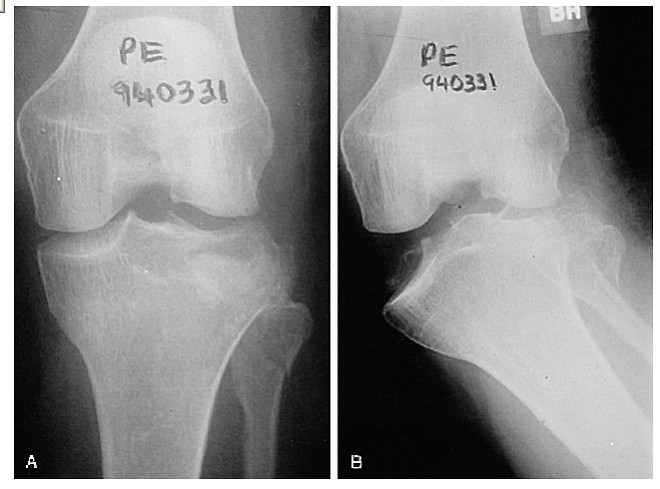

This film shows a lateral tibial plateau fracture with depression and comminution. There is a less obvious extension of the fracture through the medial tibial plateau and in fact the knee is no longer connected to the shin! |

This film shows a lateral tibial plateau fracture with depression and comminution. There is a less obvious extension of the fracture through the medial tibial plateau and in fact the knee is no longer connected to the shin! |